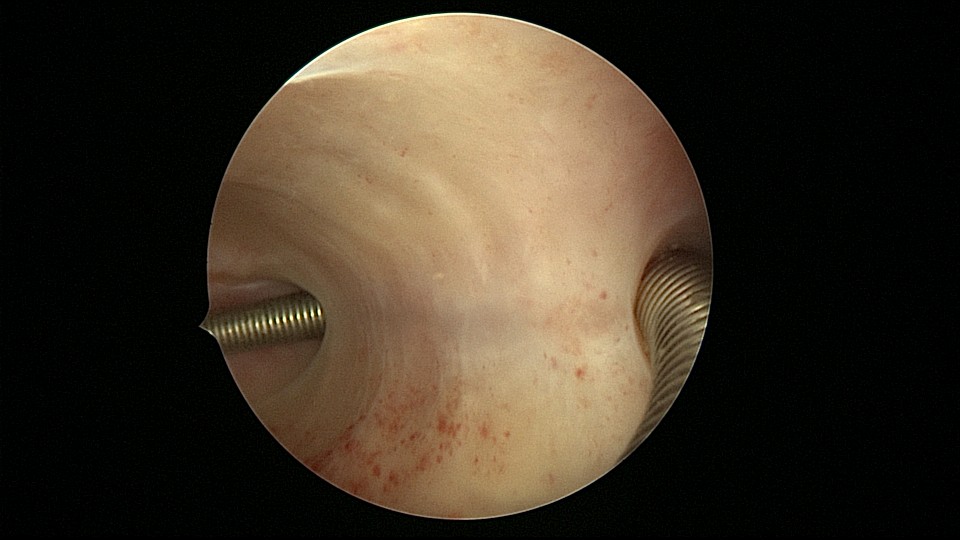

患者68岁,G3P1,顺产1次,安环42年,绝经20年,外院取环失败。子宫后位,宫颈及子宫萎缩,距宫颈内口1cm以上宫颈管封闭致密粘连,B超监护下异物钳分离粘连,打开进入宫腔的通道,艰难扩宫至6号扩宫棒,见O型环与两侧宫壁崁顿,异物钳无法取出,取环钩将环拉至宫颈外口,中弯钳牵拉,完整取出节育环,环变形,很艰难的取环经历。